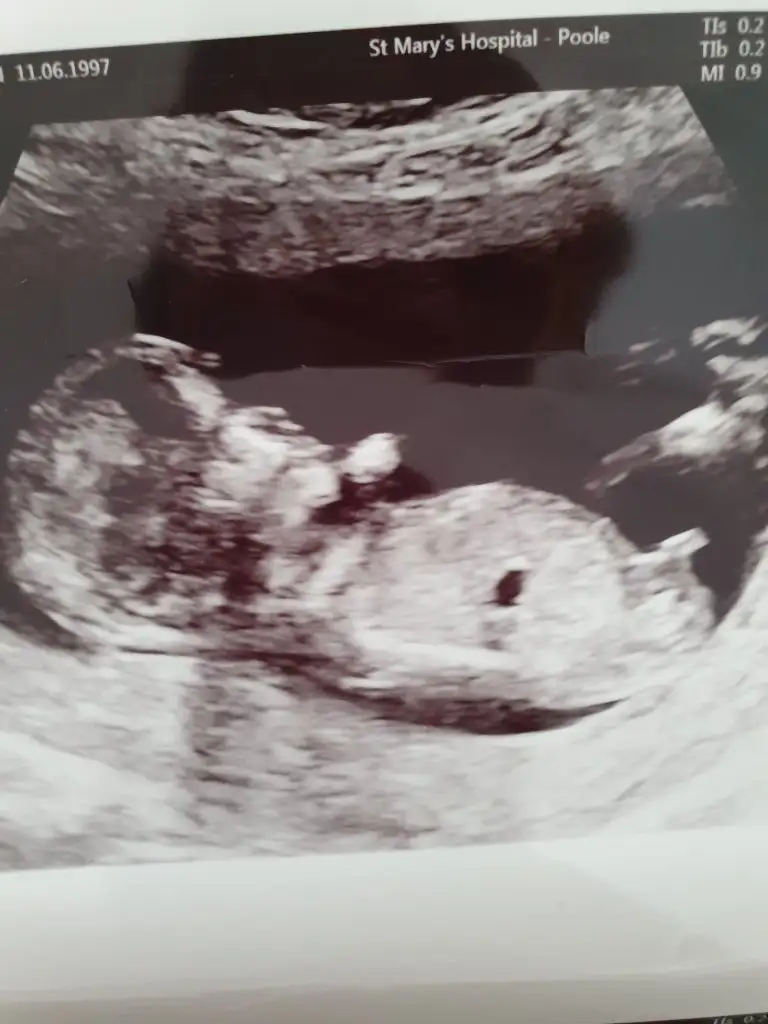

Erkek demiştim ogrendinizmi13 hafta 3 günlük rica etsem tekrar bakar mısınız Eki Görüntüle 2688103

[/B]Eki Görüntüle 473828 gordugunuz gibi ust taraftaki simgedende anlasildigi gibi eger cikinti paralel ise kiz

yok 30°lik bir aciyla yukari dogru bakiyorsa %99 oglunuz olacak demektir simdi bi kac ornek resimler daha koyacagim kiziminkide dahil

Eki Görüntüle 473829 bu bir erkek bebek genital nub cikintisi gayet yukarda

Eki Görüntüle 473831 simdi burada cikintilara bakin eger bel popo cizgisine paralel ise kiz

yok 30 derecelik bir aciyla yukari bakiyorsa erkek

Eki Görüntüle 473837 bu benim kizim cikinti gayet net ve ortada ve ben kizim diyooo